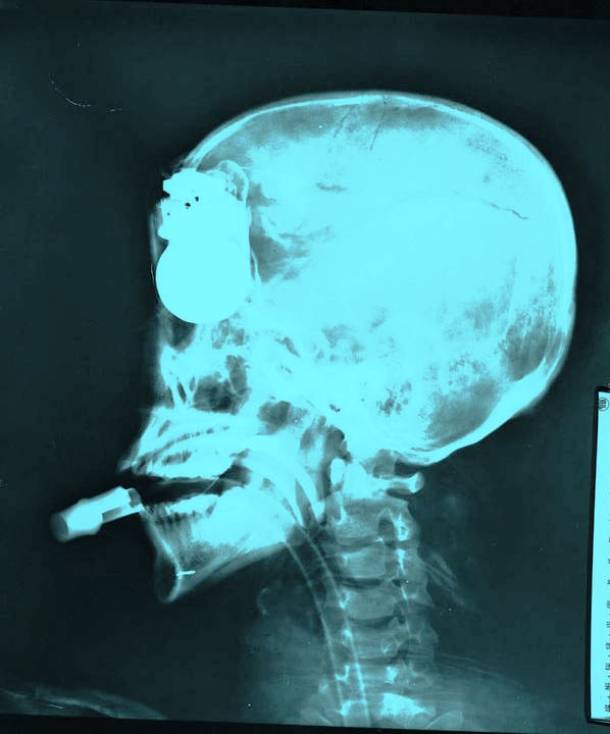

25. A Hand Grenade In The Head

We’re not exactly sure how this is even possible, or how somebody managed to survive this. But this soldier was here to prove us all wrong because here is the evidence. Here is a hand grenade, pointing through his mouth and right into the top of his skull.Advertisement